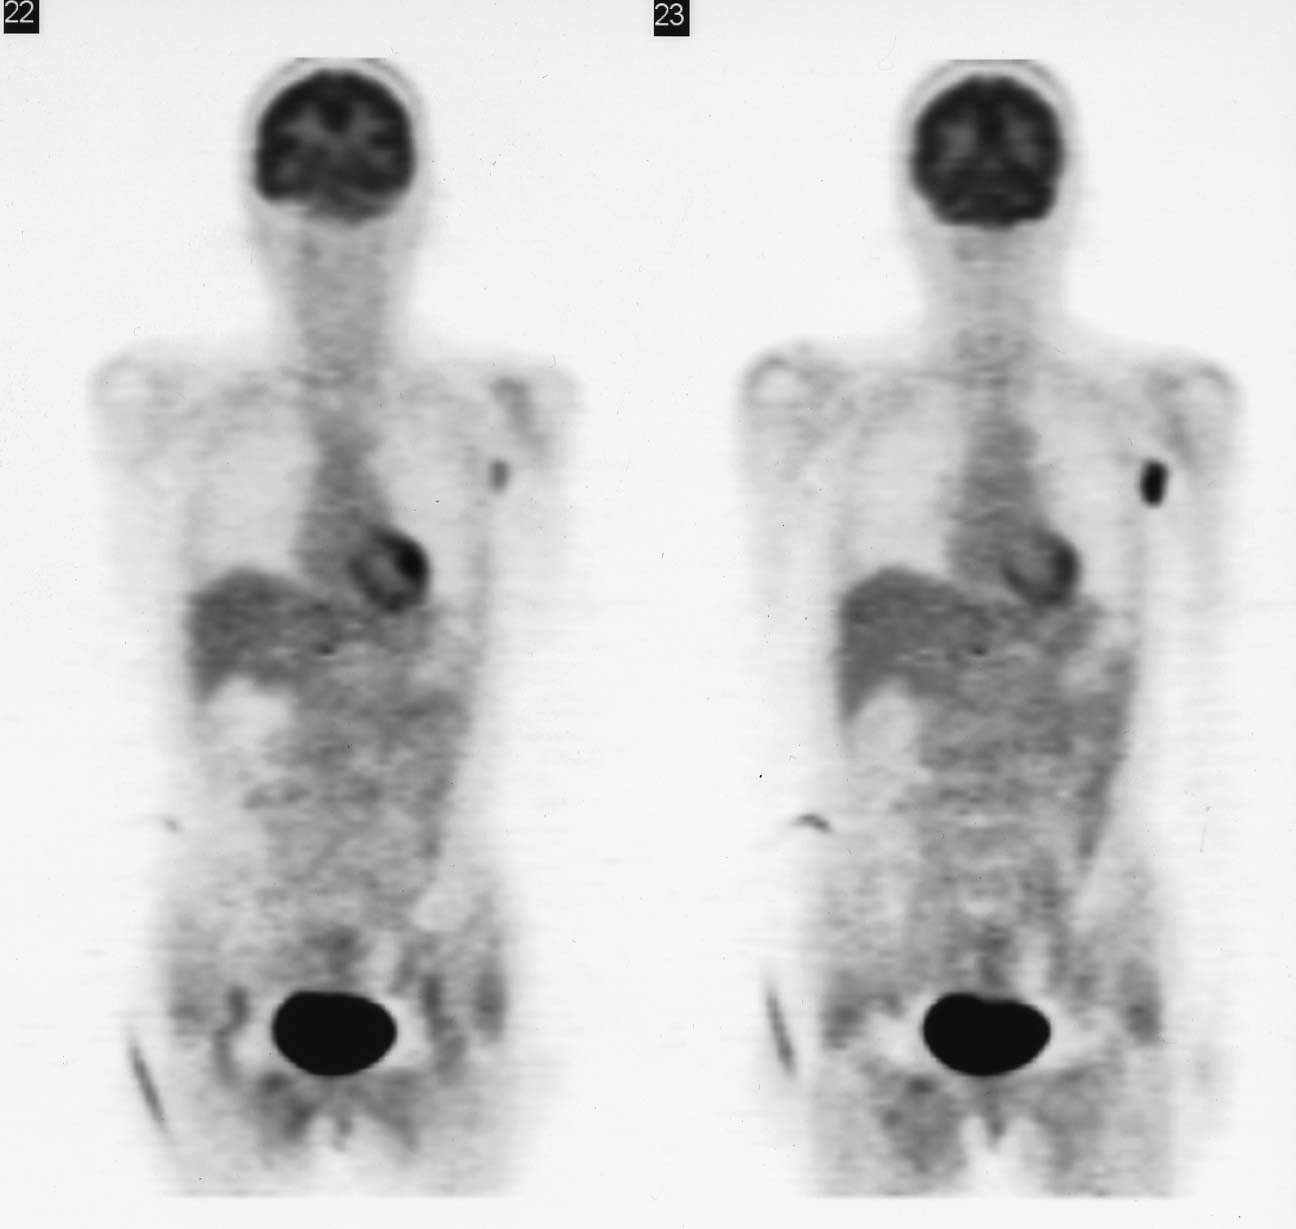

Axillary metastatic lymphnodes showing adenocarcinoma, probbably from breast cancer

- 病理診断:Metastatic carcinoma in the lymph node(原発として乳癌を最も疑う)

- 抗amphiphysin抗体陽性及び病理診断の結果から、原発巣として左乳癌を疑い、左乳房の検査(超音波、マンモグラフィ、MR)を行ったが、FDG-PET同様検出することができなかった。

- 抗amphiphysin抗体は15360倍まで低下したが(10月25日)、依然として高値を示している。結局、原発巣は確定できず、乳癌を想定した化学療法、ステロイド療法を行い、症状の軽度改善が得られている。